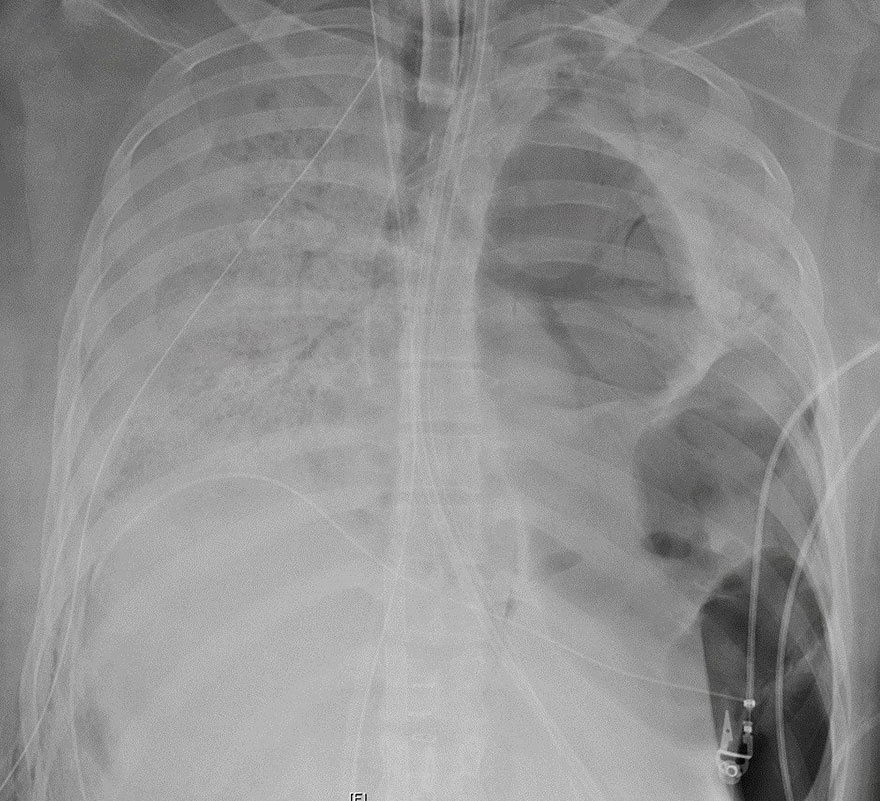

ΗΠΑ: Διπλή μεταμόσχευση πνευμόνων σε 20χρονη με κορωνοϊό (εικόνες)

ΗΠΑ: Διπλή μεταμόσχευση πνευμόνων σε μια 20χρονη βαριά ασθενή από τη νόσο Covid-19.

Μια 20χρονη, οι πνεύμονες της οποίας καταστράφηκαν «ανεπανόρθωτα» από τη νόσο Covid-19, υποβλήθηκε σε διπλή μεταμόσχευση πνευμόνων στο Σικάγο. «Η μεταμόσχευση πνευμόνων ήταν η μοναδική ευκαιρία της να επιβιώσει», δήλωσε η Έινκιτ Μπάρατ, η επικεφαλής της μονάδας θωρακοχειρουργικής στο νοσοκομείο Northwestern του Σικάγο, σε δελτίο Τύπου που εκδόθηκε μετά την επέμβαση.

Πρόκειται προφανώς για την πρώτη μεταμόσχευση αυτού του είδους στις ΗΠΑ, όχι όμως στον κόσμο, καθώς Κινέζοι γιατροί έκαναν διπλή μεταμόσχευση τον Μάρτιο.

Η ασθενής είναι μια ισπανόφωνη γυναίκα, που δεν αντιμετώπιζε κατά το παρελθόν προβλήματα υγείας, σύμφωνα με το νοσοκομείο, όμως νόσησε βαριά από τον νέο κορωνοϊό, σε βαθμό που χρειάστηκε να νοσηλευτεί 6 εβδομάδες στη μονάδα εντατικής θεραπείας.

«Για πολλές ημέρες, υπήρξε η πιο βαριά ασθενής στη μονάδα εντατικής θεραπείας Covid και πιθανόν σε ολόκληρο το νοσοκομείο», εξηγεί η Μπεθ Μάλσιν, πνευμονολόγος στο Northwestern. Ωστόσο, χρειάστηκε να περιμένουν για να γίνει η μεταμόσχευση, προκειμένου η ασθενής να βγει αρνητική στον κορωνοϊό.

«Πώς μια γυναίκα με καλή υγεία, ηλικίας περίπου 20 ετών, έφθασε σε αυτήν την κατάσταση; Έχουμε ακόμη να μάθουμε τόσα πολλά για τη Covid-19», συμπλήρωσε ο πνευμονολόγος Ρέιντ Τόμικ.